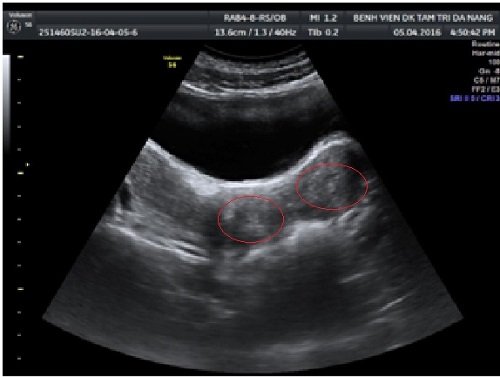

Kết quả siêu âm cho thấy bé gái có hai âm đạo, hai tử cung. Ảnh: Vnexpress |

Qua kết quả khám sơ bộ, các bác sĩ nhận thấy màng trinh của bệnh nhân bị căng và giãn rộng, âm đạo phía trên có một khối căng tím.

Ngoài ra còn có một khối căng to đè vào trực tràng, khối này tụ máu lớn lan từ tử cung đến âm đạo. Các bác sĩ chuẩn đoán bệnh nhân bị dị dạng sinh dục và vách ngăn âm đạo bị biến chứng ứ máu kinh.

Ngoài ra, qua khảo sát tử cung và buồng trứng, các bác sĩ phát hiện bệnh nhân chỉ có một quả thận bên phải.